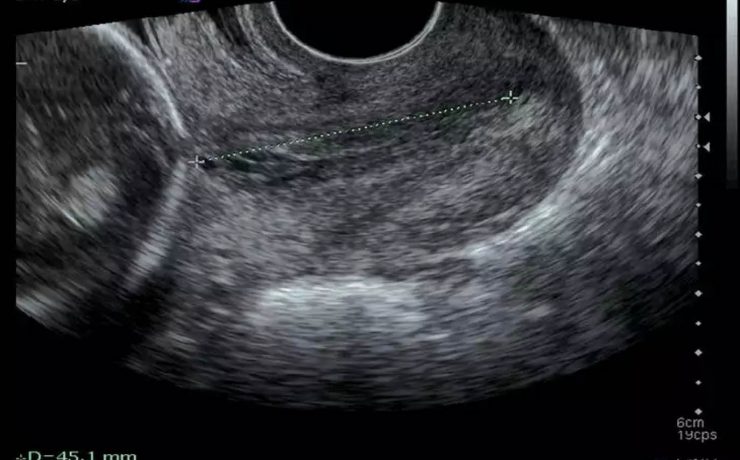

El síndrome de Rokitansky, es la anomalía más grave del tracto reproductivo femenino. Consiste en la ausencia congénita de vagina y útero ausente o rudimentario, como consecuencia de la falla en el desarrollo Mûlleriano de la vagina y el útero. Este síndrome fue descrito por Rokitansky en 1838. Es la